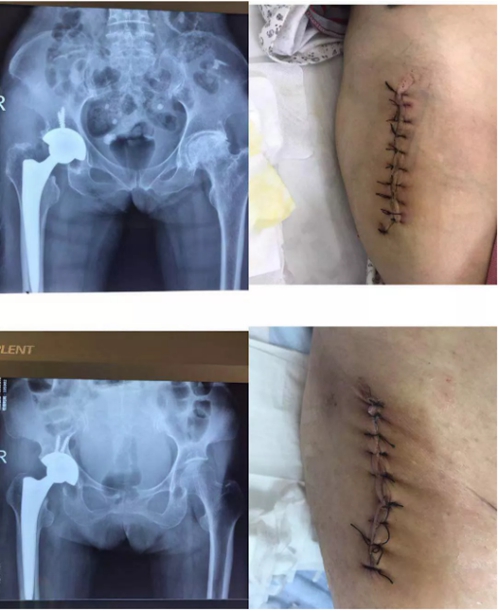

近日,我院骨一科医师团队在副院长杜敏带领下为两位老年患者在全麻下实施了微创前路髋关节置换术(DAMIS),为患者解除了病痛,手术效果良好,标志着我院骨科前路微创髋关节置换术及快速康复治疗又上了新的台阶。

微创前路髋关节置换术(DAMIS)是通过缝匠肌与阔筋膜张肌之间的肌间隙进行髋关节的显露,是一种单纯通过肌肉之间的间隙来暴露手术视野的方案,基本不损伤或影响下肢的股方肌、梨状肌、臀中肌等外旋肌群。该手术入路对于髋关节的臀中肌、梨状肌、上下孖肌、股方肌等功能肌群,以及坐骨神经等均无明显的损伤。术中不损伤肌肉组织,出血少,术后4—8小时即可下床,肌肉功能快速恢复,关节功能恢复快,术后康复快,患者术感体验较传统手术好。